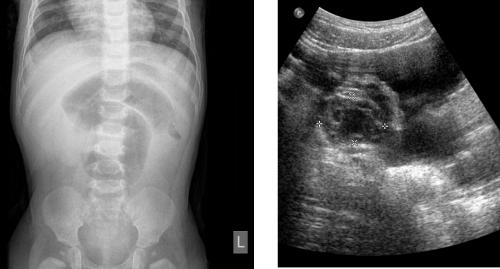

Congenital Neonatal Infected and Bleeding Hepatic Hamartoma Presenting as a Falciform Ligament Abscess, Successfully Treated by Emergency Left Hepatic Lobectomy, with Subsequent Development of Infantile Hemihypertrophy Open Access

Congenital Neonatal Infected and Bleeding Hepatic Hamartoma Presenting as a Falciform Ligament Abscess, Successfully Treated by Emergency Left Hepatic Lobectomy, with Subsequent Development of Infantile Hemihypertrophy

Govani DR, Mehta AR, Midha PK, et al.

Mesenchymal Hamartoma of the Liver (MHL) is a rare benign hepatic pediatric tumor of infancy with approximately 20% of cases diagnosed during the neonatal period, typically presenting as an enlarging abdominal mass. Rare acute complications such as intralesional bleeding and infection can lead…...